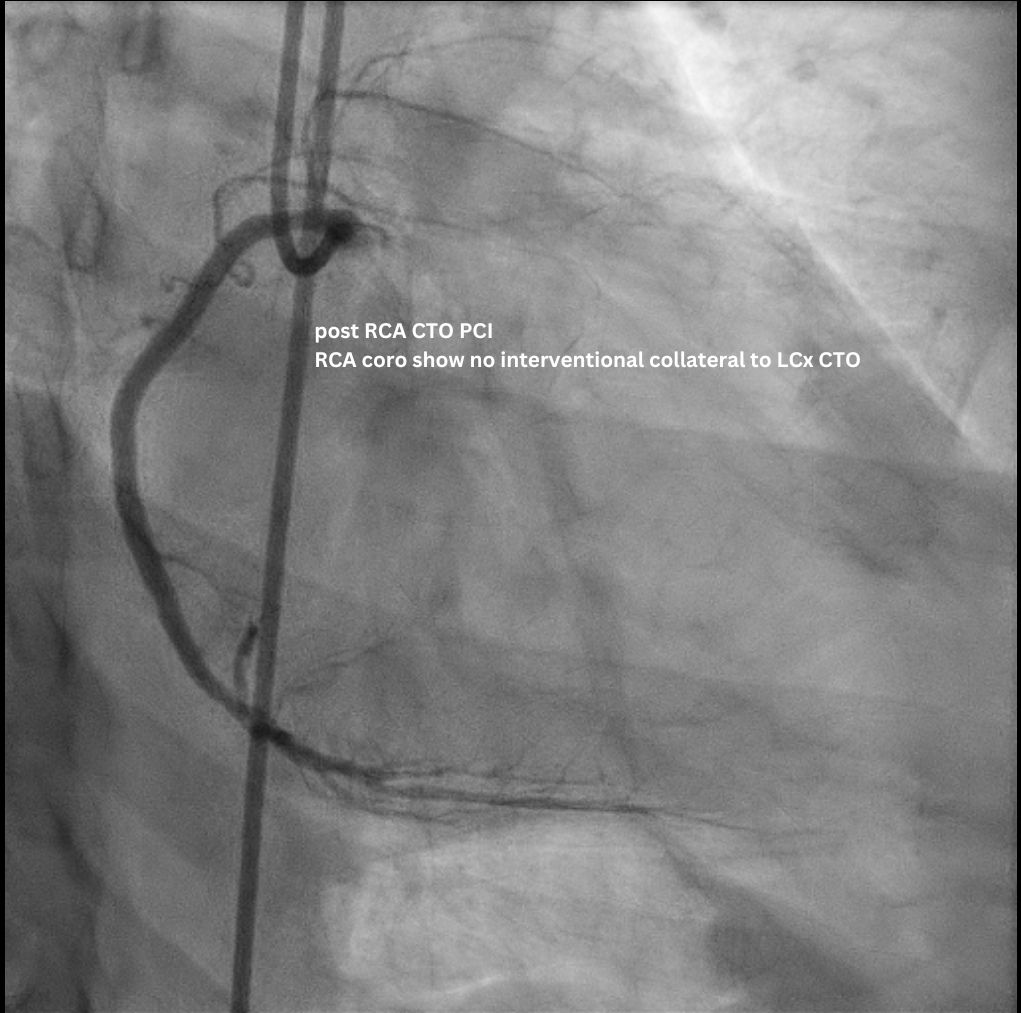

The staged PCI for the RCA CTO was completed uneventfully via an antegrade approach. Subsequent LCA angiogram showed a p-d LCx CTO supplied by an ipsilateral collateral from the D1/ LAD via an epicardial channel. RCA angiography confirmed no interventional contralateral supply. Detailed lesion analysis showed an ambiguous proximal cap (with the atrial branch as a large side branch), ~20 mm CTO length, a bend > 45¡Æ, and the distal cap located precisely at the dLCx/OM2 bifurcation.

Access was achieved via RRA and US-guided RFA puncture. A 7F SBP 3.5 guide was engaged to LM, and a 6F IL 3.5 guide was in oRCA, confirming no contralateral supply to LCx CTO. After a failed antegrade IVUS guided puncture by GW Gaia Next 2, the strategy shifted retrograde. GW Sion supported by microcatheter Caravel successfully navigated D1 across LAD stent struts, visualizing the ipsilateral epicardial collateral to OM2. The wire was exchanged to SUOH 03 and then advanced to OM2. After initial retrograde wiring failures by a UB3, a Gladius MG successfully crossed the CTO body to pLCx. IVUS to pLCx confirmed retrograde wire in subintimal plane. Multiple attempts R-CART failed in p-mLCx despite wire escalation to GW Gaia Next 3. Repeat IVUS showed enlarging pLCx hematoma, necessitating deployment of a DES (ULTIMASTER NAGOMI 3.0 mm/18 mm) to seal the entry point. Successful stent based R-CART was then achieved with Gaia Next 3, confirmed by IVUS. The IL 3.5 guide was moved to LM as an antegrade Ping-Pong guide for RG3 externalization after successfully advancing retrograde wire and microcatheter to the IL guide. The m-dLCx was prepared by SC balloons and a DES (ULTIMASTER NAGOMI 2.5 mm/50 mm) was deployed to the p-dLCx-OM2, overlapping the proximal DES. A D1 perforation was noted and then successfully treated with fat embolism via the retrograde microcatheter. Final angiogram and IVUS confirmed optimal results.